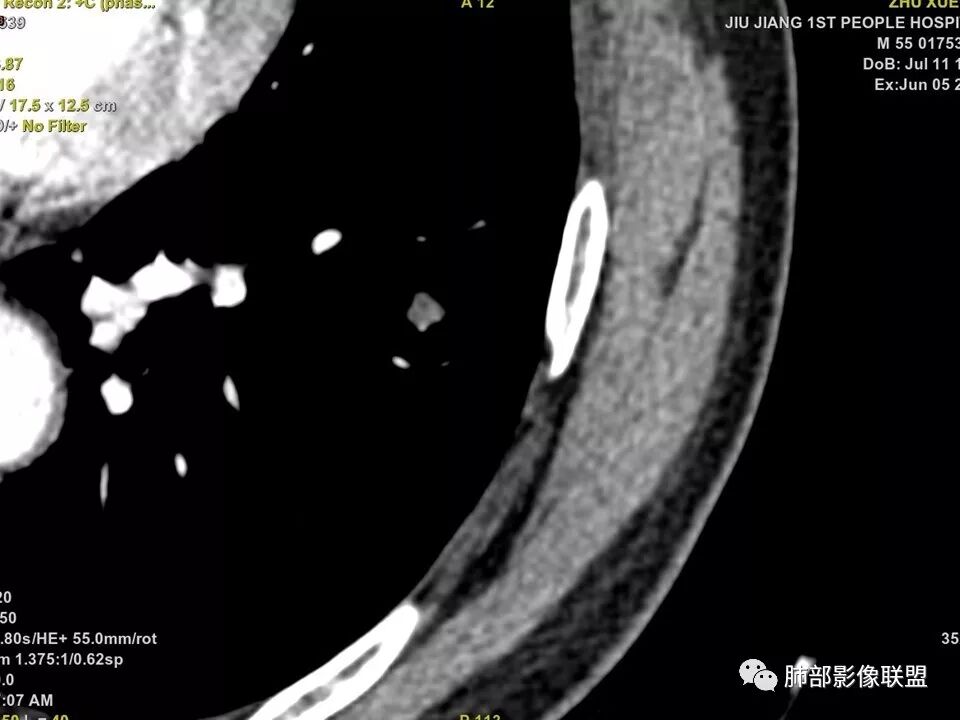

边缘有光滑,有圈黑晕,强化弱,似乎有脂肪密度,支气管截断的部位很自然,没有鼠尾状狭窄,考虑软骨型错构瘤?

病灶部分平直丶内收,有脂肪密度,不强化支持错构瘤。部分病灶有结节堆积感,分叶,与支气管、肺动脉关系密切,需鉴别腺癌。不强化进一步结核结节。

气腔内结节,其内可见脂肪成分,强化不明 I'm显,错构瘤不能除外,需要定期观察除外恶性

晨读病例,强化值小于20,还是提示良性,感觉支气管截断是坑,所以考虑错构瘤?肺癌待排

也咨询了病理科老师,肺软骨瘤来源于支气管透明软骨,理论上可以从黏膜下,突向支气管腔内生长,对支气管造成压迫性的阻塞。影像上和软骨瘤样错构瘤没法区分

典型CT特征包括:(1)圆形或椭圆形边界清楚的病灶。(2)大小1~4cm,有轻微分叶改变。(3)较均匀的软组织影,多伴有钙化。(4)无毛刺,卫星灶及肺门或纵隔淋巴结肿大。(5)CT增强扫描无强化或轻度强化,其强化可能与软骨瘤间质中的薄壁血管或周围慢性炎症反应有关。

鉴别诊断,主要是错构瘤。错构瘤是肺内最常见的良性肿瘤。错构瘤内常见“爆米花”样钙化,而软骨瘤钙化则多呈点状或环状钙化。病灶内脂肪密度影是错构瘤的特异性征象,而软骨瘤内无脂肪成分。此外尚需要与肉芽肿性炎、硬化性肺细胞瘤、肺癌、转移等鉴别。